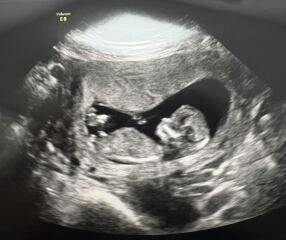

Has anyone used early glimpse for a gender prediction based on nub theory and it been right? I got this from them and really hoping it’s right! 🤞🏻I have included the original scan and a couple others I have too.

Nub theory - early glimpse